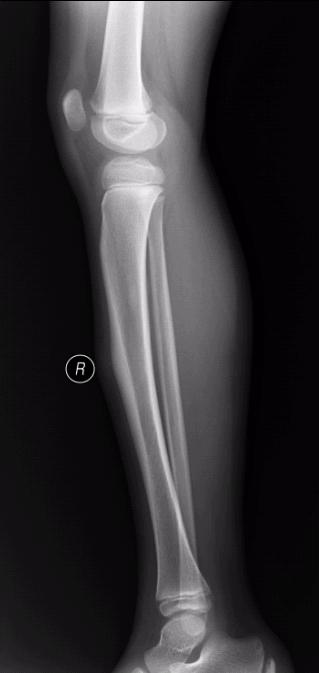

左胫骨中段前缘局限性骨皮质增厚,其内隐约见一低密度影,考虑骨样骨瘤可能,局限性骨皮质增厚可能,建议ct进一步检查。最后一张片子应该是l吧。

左胫骨前缘骨皮质增厚,有向前凸起改变,与之比较右侧胫骨皮质均匀光整。支持二楼的意见。从骨性标记看,小腿的左右标注楼主有误。

左胫骨中段前缘局限性骨皮质增厚。